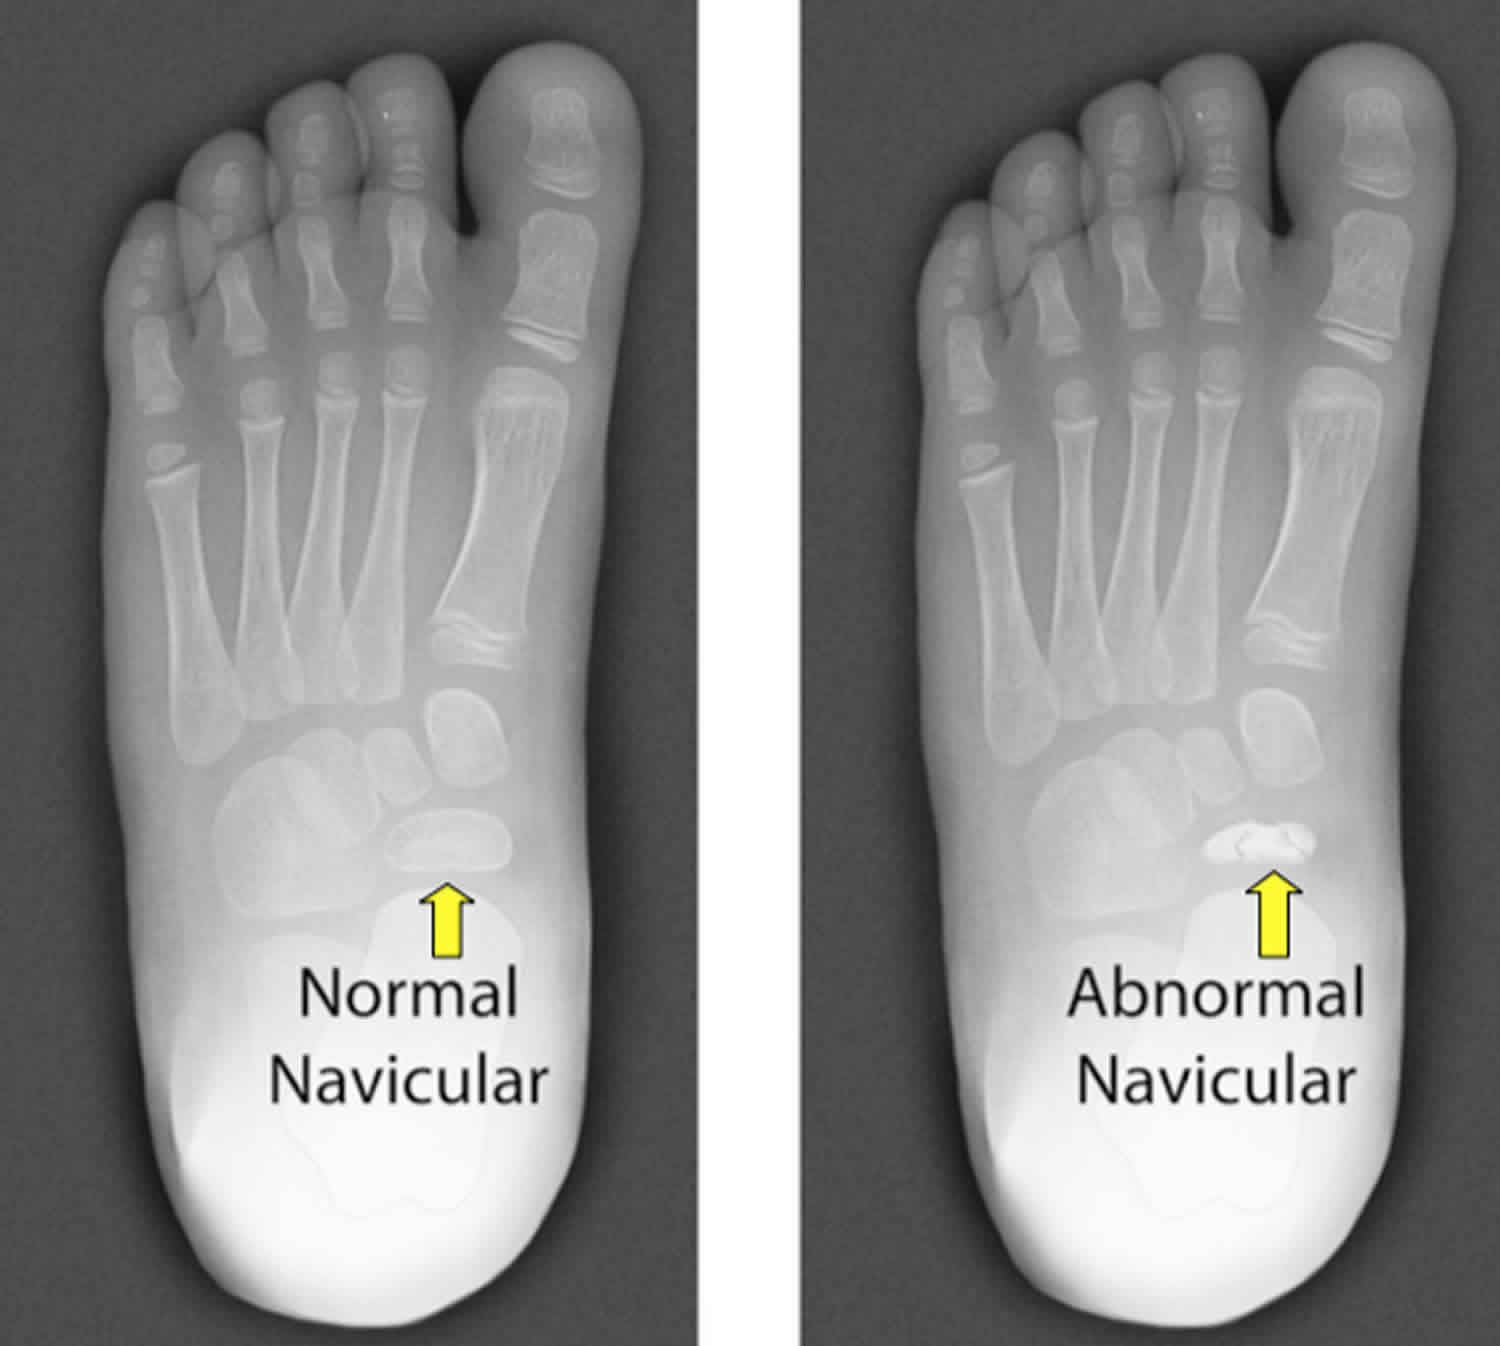

Short named as just 'Kohler's disease', it is a rare disorder of the bone characterized by stress fracture of the navicular bone during the growth phase. The resultant is limping, pain, and swelling. The commonly affected age group is 3 to 7 years old. It is more common in males as compared to female children. Typically, children may grow out of their disease with age. This condition has excellent prognosis. Reference: https://rarediseases.org/rare-diseases/kohler-disease/ Image via: https://healthjade.net/kohlers-disease/